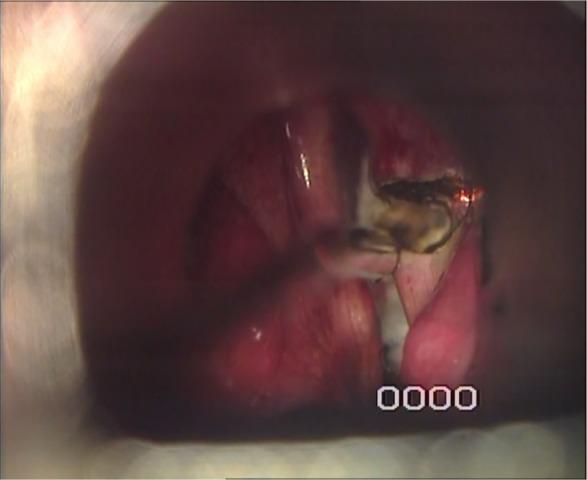

Laser Posterior Cordotomy: Is it a Good Choice in Treating Bilateral Vocal Fold Abductor Paralysis?

To assess the efficacy of CO2 laser unilateral posterior cordotomy in cases with bilateral abductor paralysis as regards improvement of dyspnea with preservation of satisfactory voice and swallowing after the operation.

Unilateral CO2 laser posterior cordotomy is an easy and effective procedure to solve the dyspnea after bilateral vocal fold abductor paralysis without aspiration or significant voice alteration.